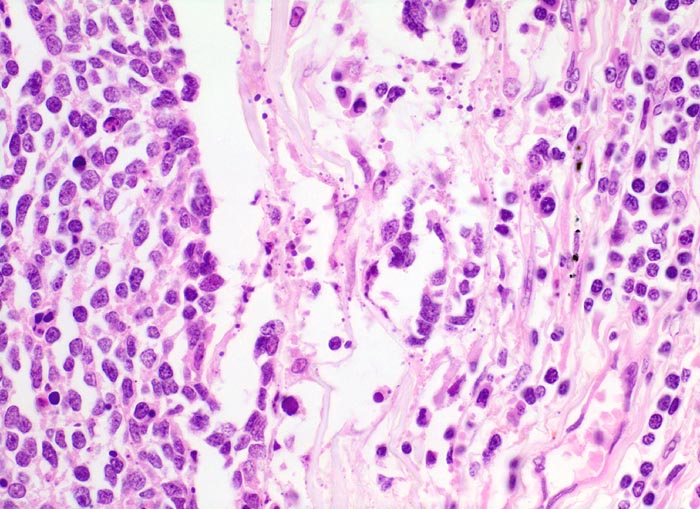

PathoPic ID 4717 - kleinzelliges Bronchuskarzinom

kleinzelliges Bronchuskarzinom

maligner Tumor

Lunge

Links im Bild die

Tumorzellen des kleinzelligen Karzinoms. Die Kerne der Tumorzellen sind etwa dreimal so gross wie die der

Lymphozyten rechts im Bild .

Inoperables metastasierendes Bronchuskarzinom. Nikotinabusus 70 Packyears.

Histologie

400